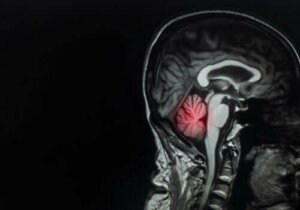

Przerzuty do mózgu: opis i leczenie tej choroby

Przerzuty do mózgu są najczęstszymi rodzajami guzów mózgu. Stanowią one spore wyzwanie dla lekarzy. W rzeczywistości stanowią one aż około 90% wszystkich przypadków nowotworów mózgu.

Szacunki medyczne wskazują, że od 10 do 40% pacjentów z rakiem dowolnego rodzaju cierpi także ma przerzuty do mózgu. Wynika to z faktu, że częstość ich występowania wzrasta, biorąc pod uwagę wyższy średni czas przeżycia chorych na raka dzięki nowoczesnym terapiom onkologicznym.

W związku z tym warto zauważyć, że rozkład cechujący przerzuty do mózgu jest wprost proporcjonalny do przepływu krwi w danym obszarze tego organu. Ogólnie rzecz biorąc przerzuty do mózgu cechują się następującymi wartościami procentowymi dotyczącymi ich występowania:

- 80% zmian nowotworowych zachodzi w mózgu

- 15% zmian zachodzi w móżdżku

- 5% zmian zachodzi w pniu mózgu